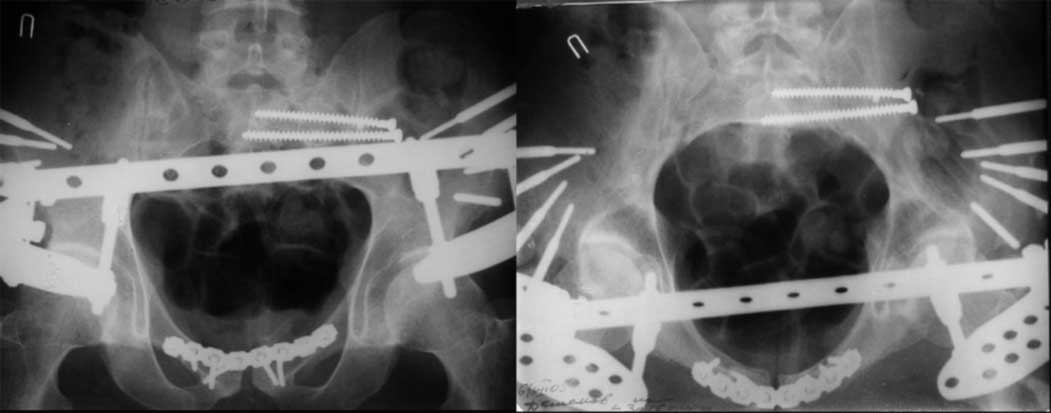

закрытое низведение правой половины таза кольцевым аппаратом (с фиксацией задних отделов), затем проведение илиосакральных винтов, реостеосинтез лонного сочленнения, дальнейшая фиксация в аппрате 2-3 мес. Похожий пример в приложении.